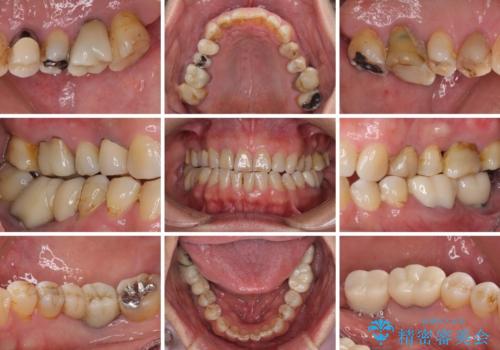

憧れの白い歯に 全顎セラミック治療

- 60歳を越え、黄ばんだ前歯をセラミッククラウンできれいな口元にしたいとのことで来院された患者様です。

診察したところ、前歯は反対咬合であり、その影響で抜歯が必要な奥歯があることが分かりました。

抜歯が必要な奥歯は、インプラント並びにブリッジにより補綴を行い、上下前歯は反対咬合を改善させるように補綴治療を行うこととしました。

健全な歯を削ってセラミッククラウンに置き換えることは、本来避けるべき治療と考えますが、今回は①患者様が60歳を越えていること、②要改善の咬合により抜歯が必要な奥歯があること、③反対咬合の前歯改善の手段としてセラミック治療が選択肢にあることなどから、全顎的なセラミック治療を行うこととしました。